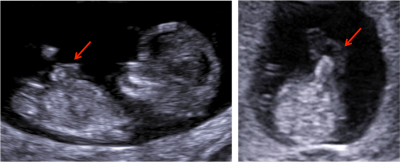

Postižení plodu rozštěpovou vadou přední břišní stěny lze často ultrazvukem zjistit již v prvním trimestru těhotenství (obrázek č. 2). V případě výskytu malé omfalokély obsahující pouze střevní kličky u plodu v jedenáctém až dvanáctém týdnu těhotenství je však vždy nutno vzít v úvahu možnost opožděného návratu střevních kliček do úponu pupečníku a raději zopakovat vyšetření za jeden až dva týdny. Pokud střevní kličky z pupečníku zmizí, byl nález variantou normálního nálezu u jinak zdravého plodu. Pokud však střevní kličky zůstanou vyhřezlé do úponu pupečníku, jedná se skutečně o omfalokélu.

Obrázek č. 2.: Ultrazvukové obrázky znázorňují defekt břišní stěny typu omfalokély u plodu ve dvanáctém týdnu těhotenství. Šipka na obrázcích směřuje ke střevním kličkám, které jsou vyhřezlé do úponu pupečníku.

(Foto: MUDr. Veronika Frisová, Profema)